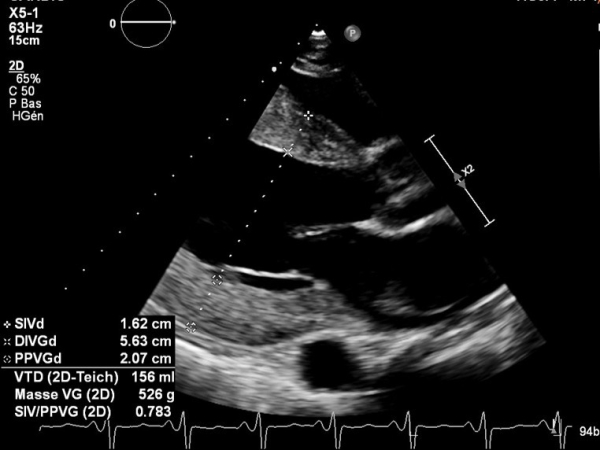

L'ETT montre :

- Dilatation modérée du VG. FEVG à 30%

- Cardiopathie hypertrophique sévère excentrique

Vidéo 3

Figure 1